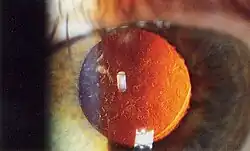

Standardeingriff um 2020 ist die kreisrunde Eröffnung (Durchmesser etwa 5 mm) des vorderen Kapselblattes, die Zertrümmerung der Linse mittels Ultraschall unter Schonung der übrigen Kapsel (Phakoemulsifikation) und die Absaugung der Trümmer. Anschließend wird in den dann leeren Kapselsack eine Kunstlinse eingesetzt. Die Kunstlinsen bestehen – im Gegensatz zu den früher gebräuchlichen Linsen aus Acrylglas – aus elastischen Materialien (beispielsweise Silikogummi oder Acrylkunststoffe), um sie in zusammengeklapptem oder gerolltem Zustand durch einen etwa 2,5 bis 3 mm großen Schnitt am Rand der Hornhaut einzusetzen, wonach sie sich im Kapselsack entfalten und mittels zweier elastischer Bügel (Haptik) von selbst zentrieren und fixieren.

.jpg)

Ohne einen adäquaten Ersatz in Form eines Linsenimplantats, so genannter Intraokularlinsen, würde man die Welt nach der Linsenentfernung in der Regel verschwommen wahrnehmen, da das Auge dann etwa 16 bis 18 Dioptrien weitsichtig wäre. Solch eine Linsenlosigkeit (Aphakie) kann mit einer Kontaktlinse oder aber – in geeigneten Fällen – auch durch eine nachträgliche (sekundäre) Kunstlinsenimplantation korrigiert werden. Sogenannte Starbrillen kommen selten und nur noch dann in Frage, wenn andere Verfahren nicht durchführbar sind.

Nach Entfernen der natürlichen Linse kann sich das Auge nicht mehr auf verschiedene Sehdistanzen einstellen (akkommodieren). Daher ist zum Lesen, wie bei der Alterssichtigkeit (Presbyopie), eine Lesebrille erforderlich. Insbesondere für junge Patienten, die bis zur Operation noch über ein volles Akkommodationsvermögen verfügten, stellt dessen Verlust durchaus eine Minderung der Lebensqualität dar. Gegenstand der heutigen Forschung sind daher zum einen Kunstlinsen, die eine gewisse Akkommodationsfähigkeit des Auges ersetzen sollen. Die bisherigen Ergebnisse sind jedoch zurückhaltend zu beurteilen. Multifokale Intraokularlinsen (zwei oder typisch drei Foki) bieten die Möglichkeit, ein „Leben ohne Brille“ zu führen, wenn die Nachteile in Form von schwachen Doppelbildern und gemindertem Kontrastsehen in Kauf genommen werden. Alternativ kann durch entsprechende Wahl der Linsenimplantate ein Zustand der Anisometropie herbeigeführt werden, der es dem einen Auge ermöglicht, in der Ferne scharf zu sehen, und dem anderen, in der Nähe (Monovision oder Goetheblick). Jedoch ist hierbei ein beidäugig scharfes Sehen, welches Voraussetzung für räumliches Sehen ist, nur bedingt möglich.